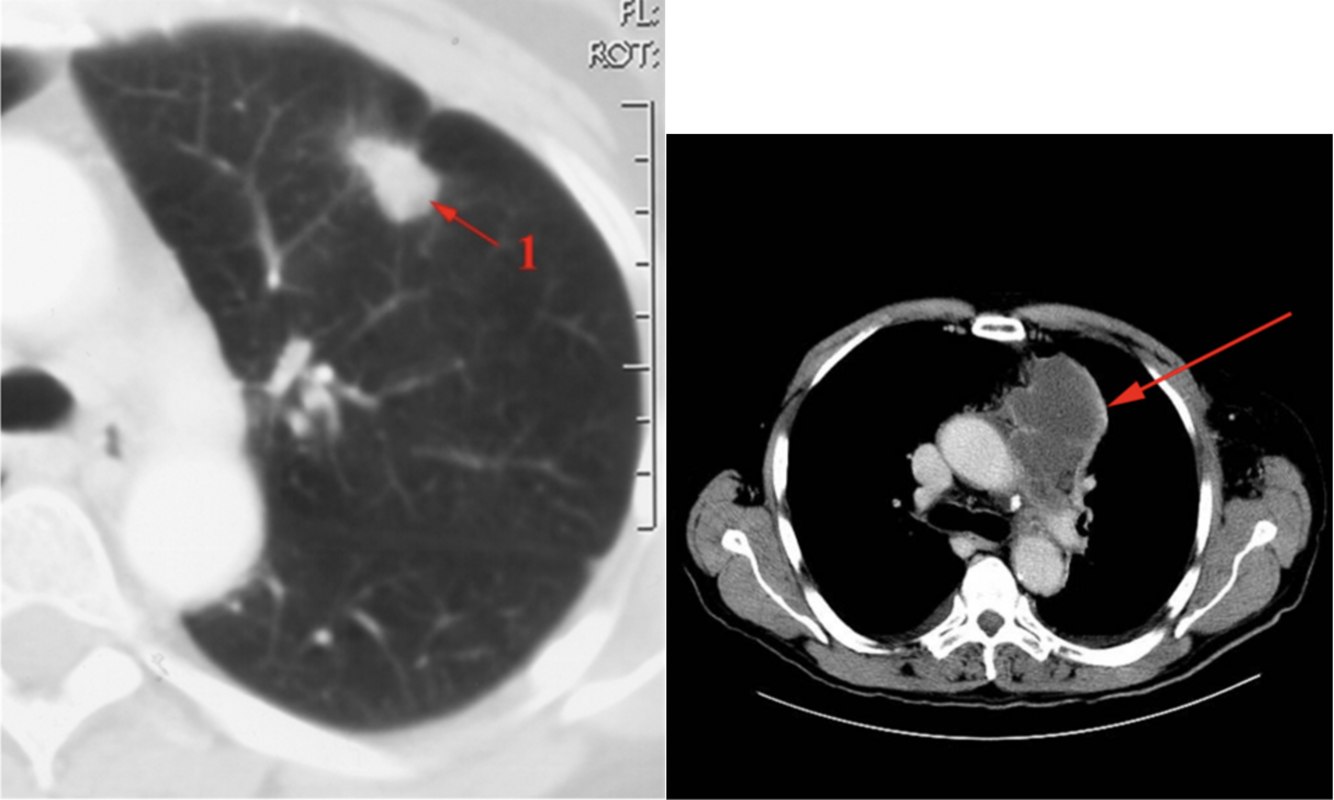

Miltraume:

Q

Diagnose?